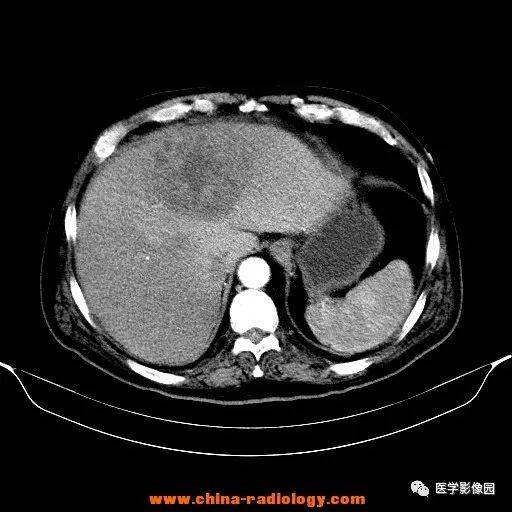

到這里,兩種肝膿腫的起因和對人體產生的損害我就和你說清楚了。綜合考慮,大爺應該是發生了肝膿腫。所謂肝膿腫是指肝內實質性組織出現細菌、阿米巴原蟲等不同病原微生物的感染出現的肝內化膿性改變,并形成膿液集聚等從而產生臨床癥狀。

肝膿腫是由致病菌通過膽道、肝靜脈、肝動脈、直接蔓延等途徑侵入肝,并在其中繁殖,從而導致的肝臟局灶性、化膿性病變,是臨床上常見的消化系統感染性疾病之一,細菌性肝膿腫最為多見。隨即醫生為大爺進行了膿腫引流術,通過引流從大爺體內引流出15ml膿液,同時進行了膿液細菌培養,使用敏感抗生素治療。

大多的肝膿腫如不及時治療,可以出現并發癥,最常見的為敗血癥,因而對于細菌性肝膿腫應及早治療。·16.對于多個、體積較小的細菌性肝膿腫患者,的治療方法是廣譜抗生。這個患者為什么又發燒了呢??我來到病房,和我的下級醫生們分析:“這個患者細菌性肝膿腫診斷沒有問題,應用抗生素療效很好,體溫正常之后又開始發燒,我們需要怎樣分析呢?首先,我們需要考慮是不是診斷錯了?不是肝膿腫?這個不可能。